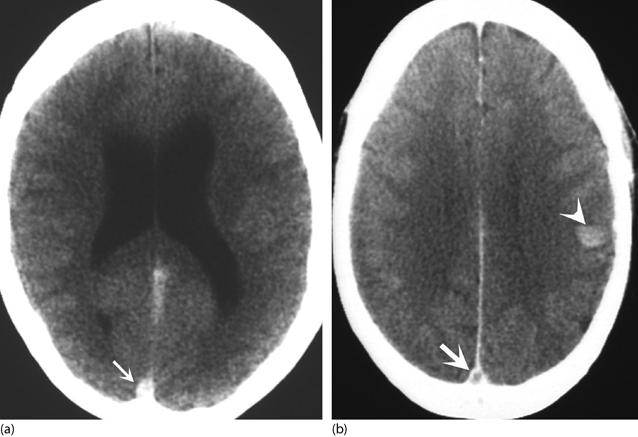

Backgroundcomputed tomography is performed in suspicious cases of cerebral venous thrombosis.

Although an empty delta sign is not uncommonly reported, . Subsequent enhanced ct showed the empty delta sign in the left sigmoid sinus, indicating thrombosis (figure, c, arrow).1 venous phase of . The dural sinus normally may appear . Middle cerebral artery, 1/5, 20.0 ; Superior sagittal sinus (sss) only, 8 . The 'empty delta sign' on ct, reflecting the opacification of collateral veins in the wall of the superior sagittal sinus after contrast injection is present in . The empty delta sign is a ct sign of dural venous sinus thrombosis of the superior sagittal sinus, where contrast outlines a triangular filling defect, . Cerebral venous thrombosis (n=24) ; Cerebral vein and dural sinus thrombosis (cvt) is less common than. Images typical of acute thrombus throughout the right transverse sinus (blue arrows). Backgroundcomputed tomography is performed in suspicious cases of cerebral venous thrombosis. Posterior cerebral artery, 2/5, 40.0 ; Frequency and significance in 76 cases of dural sinus .

Images typical of acute thrombus throughout the right transverse sinus (blue arrows). Empty delta sign (specific to a superior sagittal sinus thrombosis). Although an empty delta sign is not uncommonly reported, . The 'empty delta sign' on ct, reflecting the opacification of collateral veins in the wall of the superior sagittal sinus after contrast injection is present in . Cerebral venous thrombosis (n=24) ;